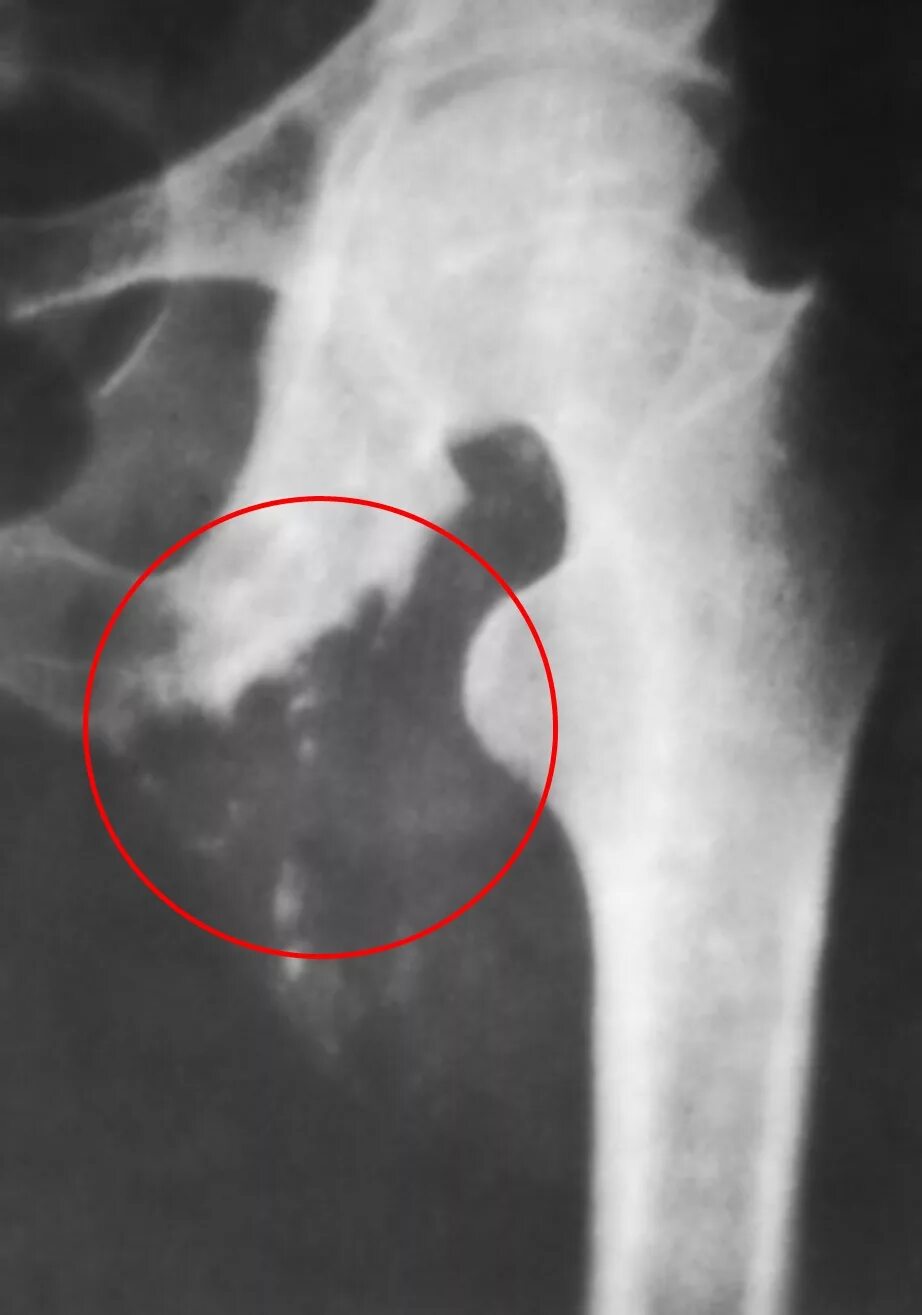

Туберкулез суставов симптомы